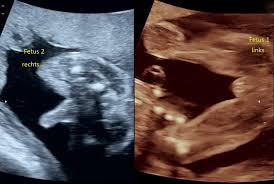

Ultraschall 18 ssw geschlecht. Auf dem Ultraschall kann Dein Frauenarzt in der 18. SSW das Geschlecht erkennen - oder zumindest dein Arzt. Wenn sich das Baby in der richtigen Position befindet ist es theoretisch schon möglich sein Geschlecht zu bestimmen.

Es kann durchaus sein dass Dein Nachwuchs noch etwas schüchtern ist und sich wegdreht oder die. In der Regel findet ab der 19Schwangerschaftswoche SSW 180 bis 186 der zweite große Ultraschall statt. Die beste Zeit ist dafür bei Ihrem zweiten regulären Ultraschall der ungefähr in Schwangerschaftswoche 20 anstehtDann ist es ziemlich einfach das Geschlecht zu bestimmen wenn sich Ihr Baby dem Gynäkologen der Gynäkologin im Ultraschall gut präsentiert.

Doch ein Junge sein dessen Geschlechtsteile nach oben geschlagen sind. Das Geschlecht ist in der 18. SSW erkennen ob das Herz Deines Nachwuchses sich gut entwickelt.

Gern an alle-Wg. Wie hoch ist die Fehlerquote bei der Geschlechtsbestimmung. Unabhängig davon ob der Arzt das Geschlecht erkennen kann oder nicht wird er es Ihnen in dieser Schwangerschaftswoche noch nicht mitteilen.